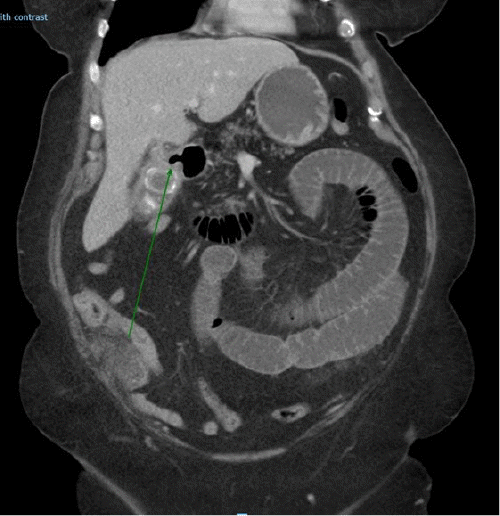

On examination, her heart rate, blood pressure, temperature, and oxygen saturation were all within normal limits. Clinically, her abdomen was distended and mildly tender. Hematological and biochemistry tests were ordered, revealing a raised white cell count (WCC) of 12.0 mmol/L (4.0-11.0 mmol/L), a C-reactive protein (CRP) of 115mg/L (0-5mg/L) and a cholestatic profile in her liver function tests (LFTs) with alkaline phosphatase (ALKP) of 117 U/L (30-110 U/L) and gamma-glutamyl transferase (GGT) of 233 U/L (5-35 U/L). A computed tomography (CT) scan demonstrated cholelithiasis, a cholecystoduodenal fistula, and gallstone ileus with an obstructing gallstone in the distal jejunum (Figure 1). Following resuscitation, an emergent laparotomy and enterolithotomy were performed for an obstructing 4.5 cm gallstone in the distal jejunum. No further stones were palpable in the remaining small bowel, only within the gallbladder. After an uncomplicated postoperative recovery, our patient was discharged home on day seven with outpatient follow-up arranged.

Figure 1. CT Scan Demonstrating Gallstone Ileus with Obstructing Stone in Distal Jejunum and Cholecystoduodenal Fistula (arrow). Published with Permission